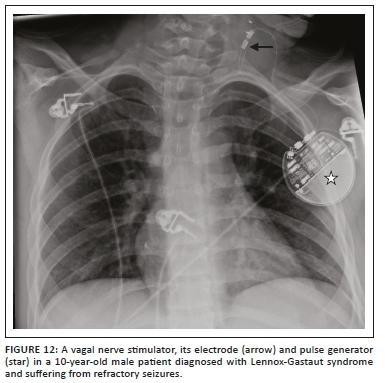

Medical devices and materials such as electrocardiogram (ECG) leads, ventilator tubing, syringes, clamps, temperature sensors, post-coronary artery bypass grafting (CABG) sternotomy wires, surgical clips, orthopaedic implants, gown snaps, etc. are commonly seen on CXRs. Because of its limited scope, we have not included cardiac devices in this article. However, there are other non-cardiac iatrogenic objects that can be seen on CXRs and these have been summarised in Table 2. Radiologists need to recognise them, be aware of their function and look for any related complications.